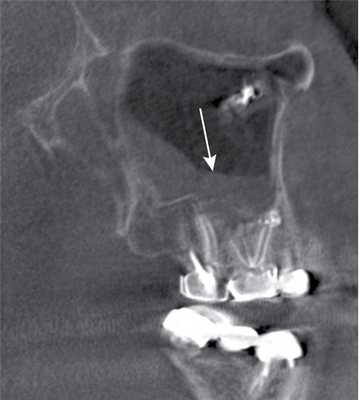

Пломбировочный материал был обнаружен у 38 (22,8%) пациентов (рис. 2). Из них у 34 (20,4%) больных в подслизистом слое нижней стенки синуса, у 4 (2,4%) — в верхнем отделе у медиальной стенки синуса (рис. 3). У 8 (4,8%) пациентов диагностированы ошибки стоматологической имплантации: верхушка импланта была погружена в полость синуса, что стало причиной развития хронического одонтогенного верхнечелюстного синусита, а также осложнений в виде хронического полисинусита (n=4; 2,4%).

Рис. 3. КЛКТ. Сагиттальная реконструкция, правый верхнечелюстной синус. Пациент У., 48 лет. Диагноз: правосторонний одонтогенный хронический верхнечелюстной синусит. Зубы 1.6 и 1.7 после эндодонтического лечения, отмечается выведение пломбировочного материала за верхушки корней зуба 1.6 (материал располагается в костной ткани альвеолярного отростка и в подслизистом слое синуса). Определяется разрежение костной ткани в области корней 1.6 и 1.7, костная стенка синуса в данной области не прослеживается (стрелка). В нижнем отделе синуса определяется утолщение слизистой оболочки до 10 мм, в верхнемедиальном отделе синуса визуализируется инородное тело неправильной формы металлической плотности (соответствует фрагментам пломбировочного материала).